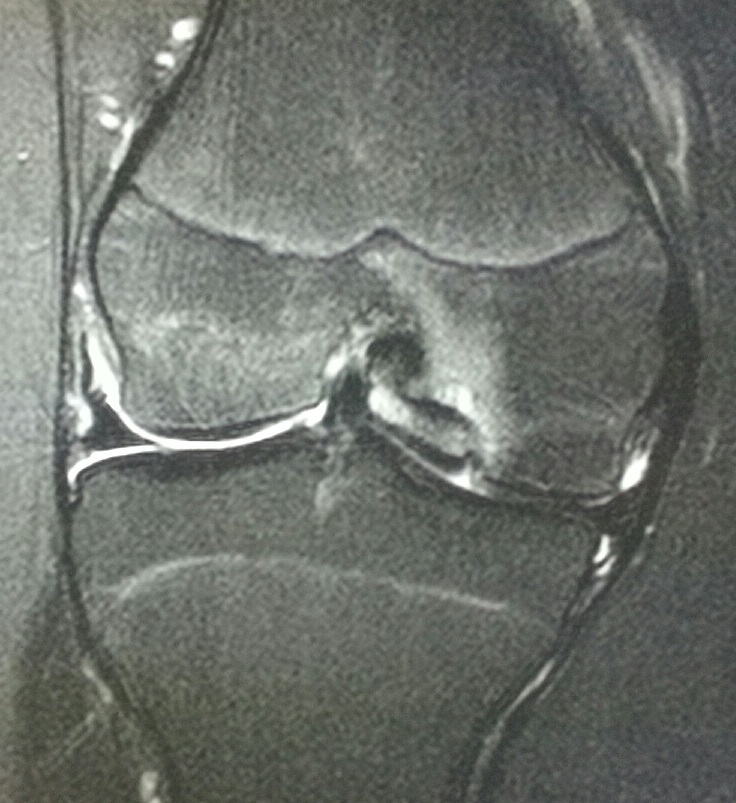

Upon further inspection, an MRI was ordered. T1 (Figure 3) and T2 (Figure 4) weighted images were obtained. On the T2 weighted images, there is edema in the adjacent abnormal medial femoral condyle and in the region of sclerosis. The fragment appears to be more displaced laterally on the T1 weighted images versus the T2 weighted images, which strongly implies a loose type of osteochondral injury.

Figure 4. T2 weighted MRI of the right knee in the coronal plane.

Osteochondrosis dessicans (OCD) is a type of avascular necrosis in which the blood supply to the bone in the affected area is disrupted with subsequent resorption of bone and fragmentation of the overlying cartilage. The bone deprived of its blood supply shrinks in size and can separate or fragment from the parent bone. The fragments of overlying cartilage can become loose bodies within the joint leading to “catching or locking.”

This patient was referred to orthopedics for treatment. Given that the injury is unstable, surgical fixation of the abnormal fragment from the lateral aspect of the medial femoral condyle to the parent bone is being strongly considered.